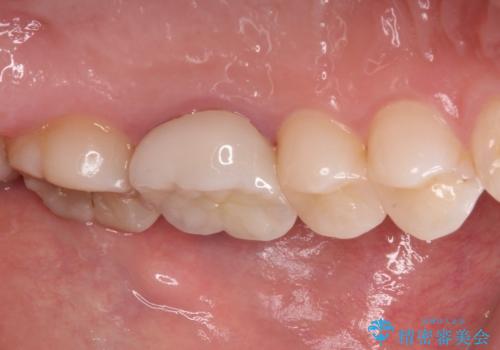

口腔内から、土台も含め銀歯がなくなったことでメタルフリーとなりました。